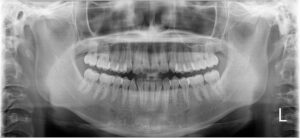

②レントゲン撮影

口全体が映るパノラマレントゲンを撮影します。

レントゲン写真も矯正前→現在で並べてみます。

ぎゅうぎゅうに詰まっていたのが少し緩和されています。

歯根の吸収もないようで一安心です。